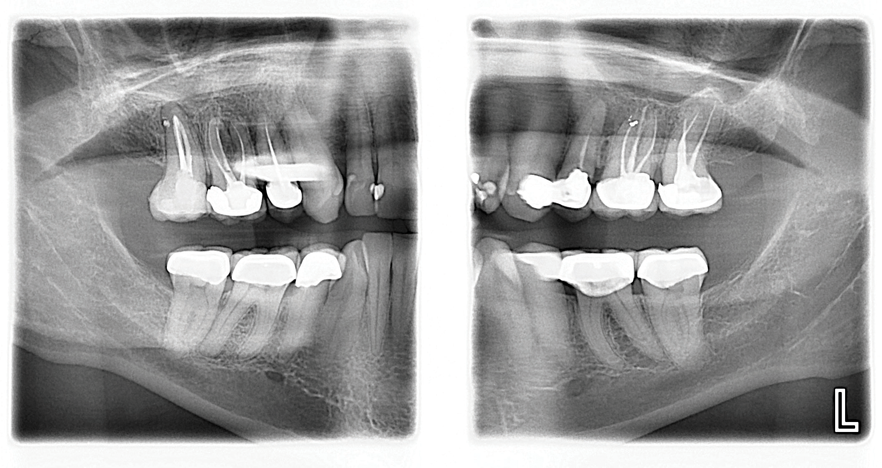

A 56-year-old female patient required an extensive treatment plan, including multiple crowns and fillings in each quadrant. She was able to complete treatment only in stages. By the time one quadrant was completed, she began to have pain on the mesial of tooth No. 20 (Figure 1 and Figure 2). Because the patient had no more dental benefits for the year, she needed to alleviate the sensitivity and prevent further problems between appointments. The doctor recommended SDF to stave off the sensitivity she was experiencing and to prevent growth of the lesion. Silver diamine fluoride was placed during a restorative appointment, and her sensitivity and pain subsided. When she returned a month later for her hygiene visit, she stated her pain had returned. A second SDF treatment was administered, which prevented the pain from returning a third time, until her restorative treatment could resume.

(1.) Patient exhbitied pain on the mesial of tooth No. 20.

Figure 1

(2.) Patient required an extensive treatment plan, including multiple crowns and fillings in each quadrant.

Figure 2